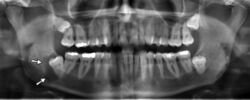

Panoramic radiograph showing horizontally impacted lower wisdom teeth.

Minimally-displaced fracture in right mandibular. Arrow marks fracture, root canal on central incisor, teeth to the left of fracture do not touch

Panoramic radiograph showing Stafne defect (arrowed).